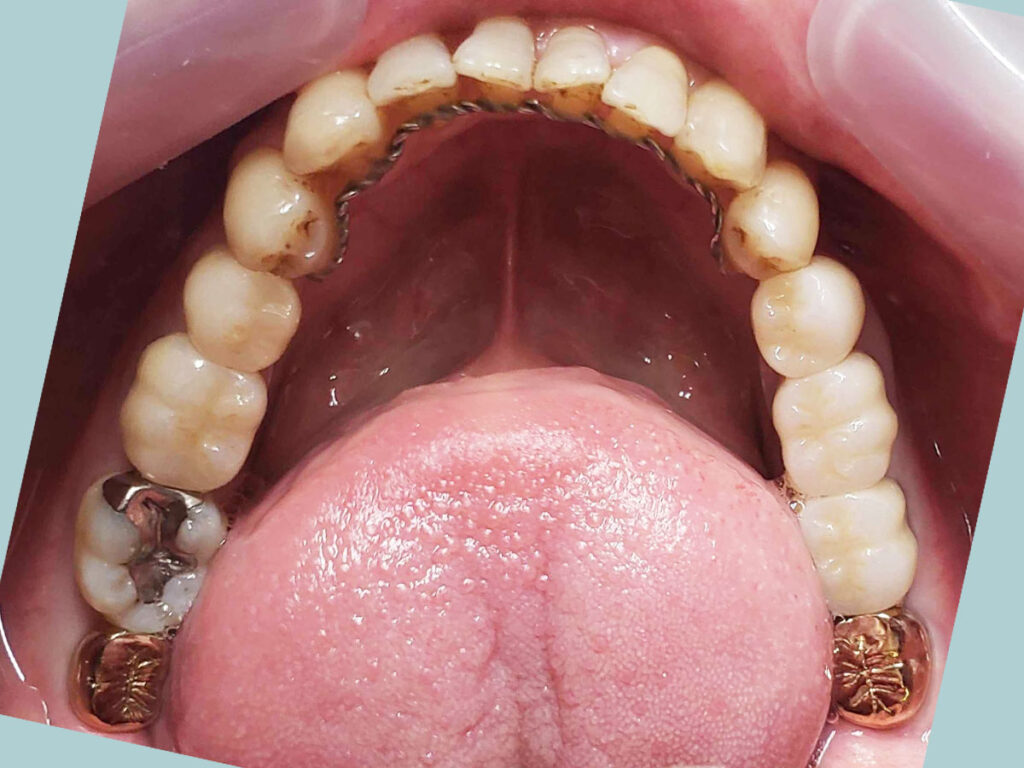

術前

- 矯正診断:3級骨格性の反対咬合

- 治療方針:以前に治療したほぼ全ての歯の再治療(虫歯治療、歯内療法、歯周処置)、矯正用インプラントを用いたワイヤー矯正、修復処置(被せ物)、保定(上マウスピース、下ワイヤー)、メンテナンス